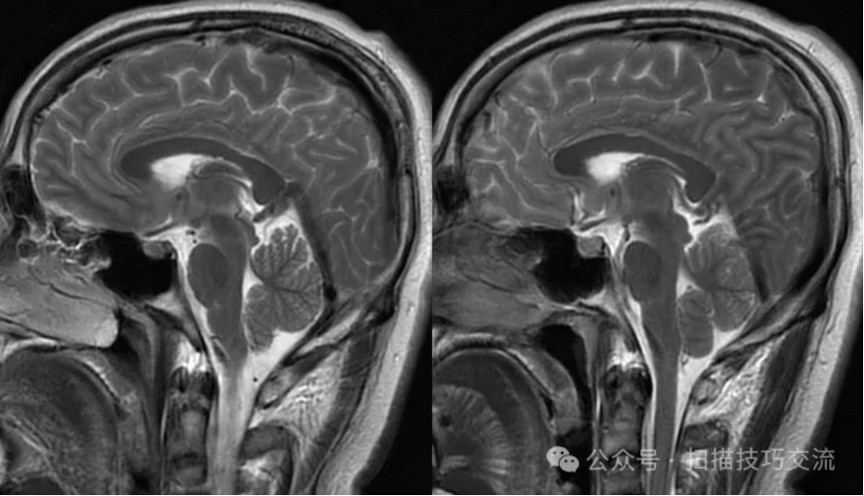

临床申请:颅脑平扫,静脉成像,磁敏感成像,颅内静脉血管黑血成像。

颅内静脉黑血成像,CUBE T1fs w/o +c,静脉窦未见异常。